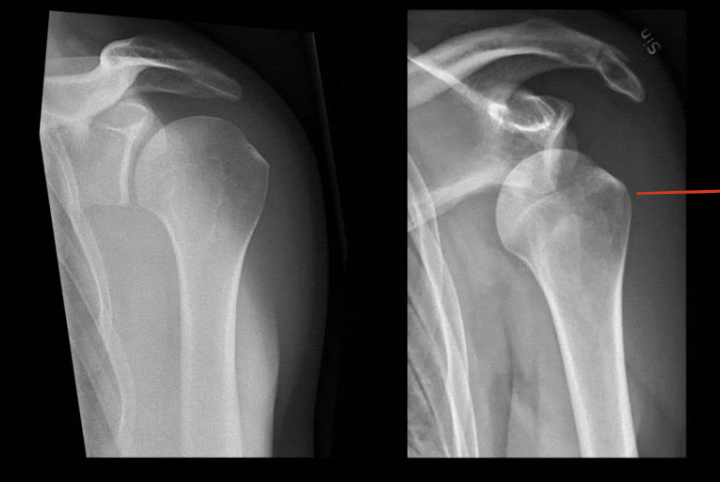

Identify 4 joints ? What view? WHAT IS THAT ?

Sholder Joint

AcromioClavicular Joint

ThoracoScapular Joint

SternoClavicular Joint

— Antero-Posterior View

— X-ray of shoulder

Identify the structures ? name of the bone ?

— Humerus

• 1, Clavicle.

• 2, Acromion.

• 3, Greater tubercle.

• 4, Lesser tubercle.

• 5, Neck of the humerus

• 6, Humerus.

• 7, Coracoid Process.

• 8, Scapula

• 9, Rib.

• Arrow, Glenohumeral joint space.

Identify the structures ? name of the bone ? View?

— Antero-Posterior